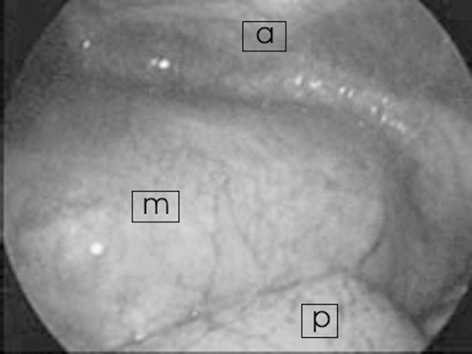

Varón de 14 años que en las 24 h previas a su ingreso presenta un dolor torácico agudo con disnea que aumenta con el decúbito supino. Previamente a este episodio había estado asintomático. En la exploración lo único destacable fue un soplo II/VI. En la radiografía de tórax se vio ensanchamiento mediastínico, sugerente de masa en mediastino anterior, motivo por el cual se decidió ingreso y realización de tomografía computarizada (TC) torácica urgente (fig. 1). En este estudio se observa una masa de 12×13×18 cm mediastínica anterior, en región prevascular, de característica sólida, heterogénea y acompañada de un derrame pleural izquierdo de escasa cantidad. Los estudios de laboratorio, hemograma y marcadores tumorales (α -fetoproteína y β -gonadotropina coriónica humana) fueron normales. Se realiza estudio cardiológico en el que lo único objetivable es una leve obstrucción a la salida del ventrículo derecho. Ante estos hallazgos se decidió biopsia tumoral y estudio de la médula ósea. El diagnóstico anatomopatológico dio como primera posibilidad teratoma quístico maduro, sin poder descartar quiste tímico multilocular. La médula ósea fue normal. Bajo anestesia general, se realizó toracoscopia colocando al paciente en decúbito lateral derecho. No se realizó intubación selectiva. Se emplearon 4 trócares de 5 mm y una óptica de 30°. No se encontraron adherencias pleurales, el colapso del pulmón se consiguió mediante neumotórax controlado de 8-10 mmHg, sin que éste provocara alteraciones gasométricas. La posterior retracción del pulmón dejó ver una tumoración de gran tamaño que ocupaba el compartimiento anterior del mediastino en vecindad con el pericardio (fig. 2). El tumor se encontraba adherido a la pared anterior torácica sobre la zona de la biopsia previa, pero no se observó invasión de los tejidos adyacentes. Se comenzó la disección de la tumoración por su porción más basal separándola del pericardio sin dañar éste, evitando el sangrado mediante el empleo de un dispositivo de sellado de vasos (ligasure). La disección se completó hasta su conexión extratorácica con el tejido tímico. La masa se introdujo en una bolsa de laparoscopia y se extrajo ampliando una de las incisiones de los trócares. Se colocó un tubo de drenaje endotorácico que se retiró a los 2 días. El postoperatorio trascurrió sin complicaciones y fue dado de alta asintomático. La pieza se diagnosticó de teratoma quístico maduro. En revisiones posteriores el paciente presentó buen estado general, heridas de buen aspecto y sin recidivas tras año y medio.

Figura 1.TC torácica: masa heterogénea, prevascular en mediastino anterior. Mínimo derrame pleural izquierdo.